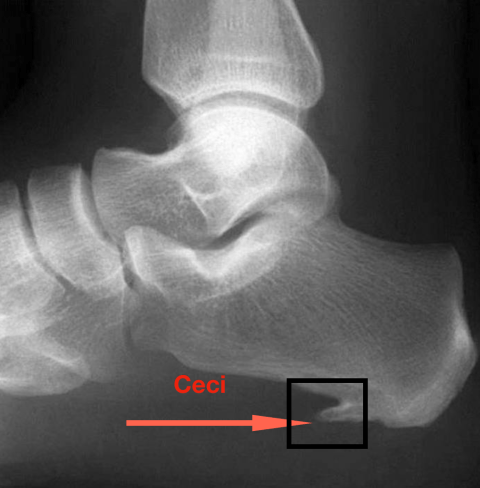

Eh bien non, il s’agit de ceci ! Et qui ne « pique » pas…

Qu’en est-il de cette fameuse épine qui ne pique pas ? L’épine de Lenoir est une trouvaille radiologique. Elle se situe à l’origine de l’insertion des courts fléchisseurs des orteils. Elle est observable chez 50 % des cas de fasciite plantaire et chez 15 % de la population asymptomatique. Elle n’entraîne pas de douleur en soi et il n’y a pas de lien précis entre l’épine et la fasciite (aponévrosite plantaire).